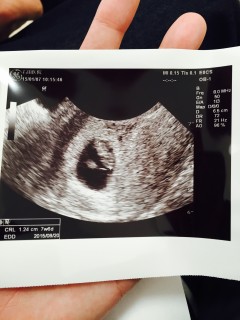

先々週の初診で4w5dぐらいだと言われたのですが、CRL=10.1mmで大体8週ぐらいだと言われました。元々生理不順で、基礎体温もストレス軽減の為にやめていたので、自分で排卵日がわかっていませんでした(汗)無事に心拍も確認できたので、2週間後の初期検診で出産予定日が確定します☆

一回目の初検診の時は赤ちゃんの袋しか確認できなくて二週間待つの長かった。 無事心拍も確認できて安心。 これからの成長も楽しみ